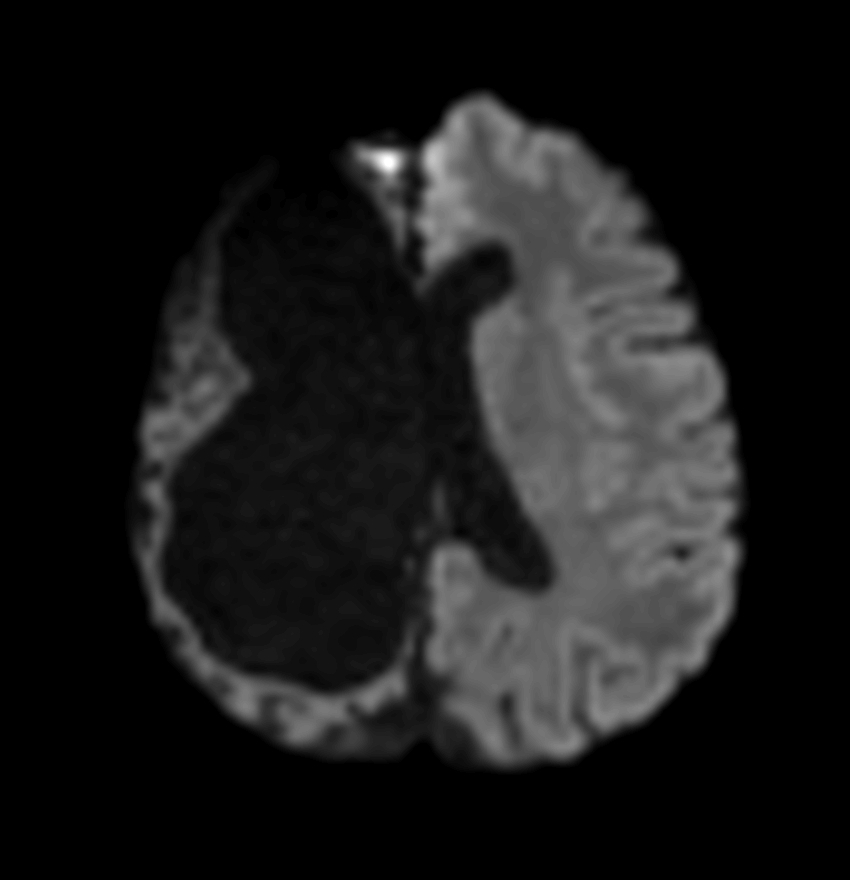

Axial DTI (ADC)